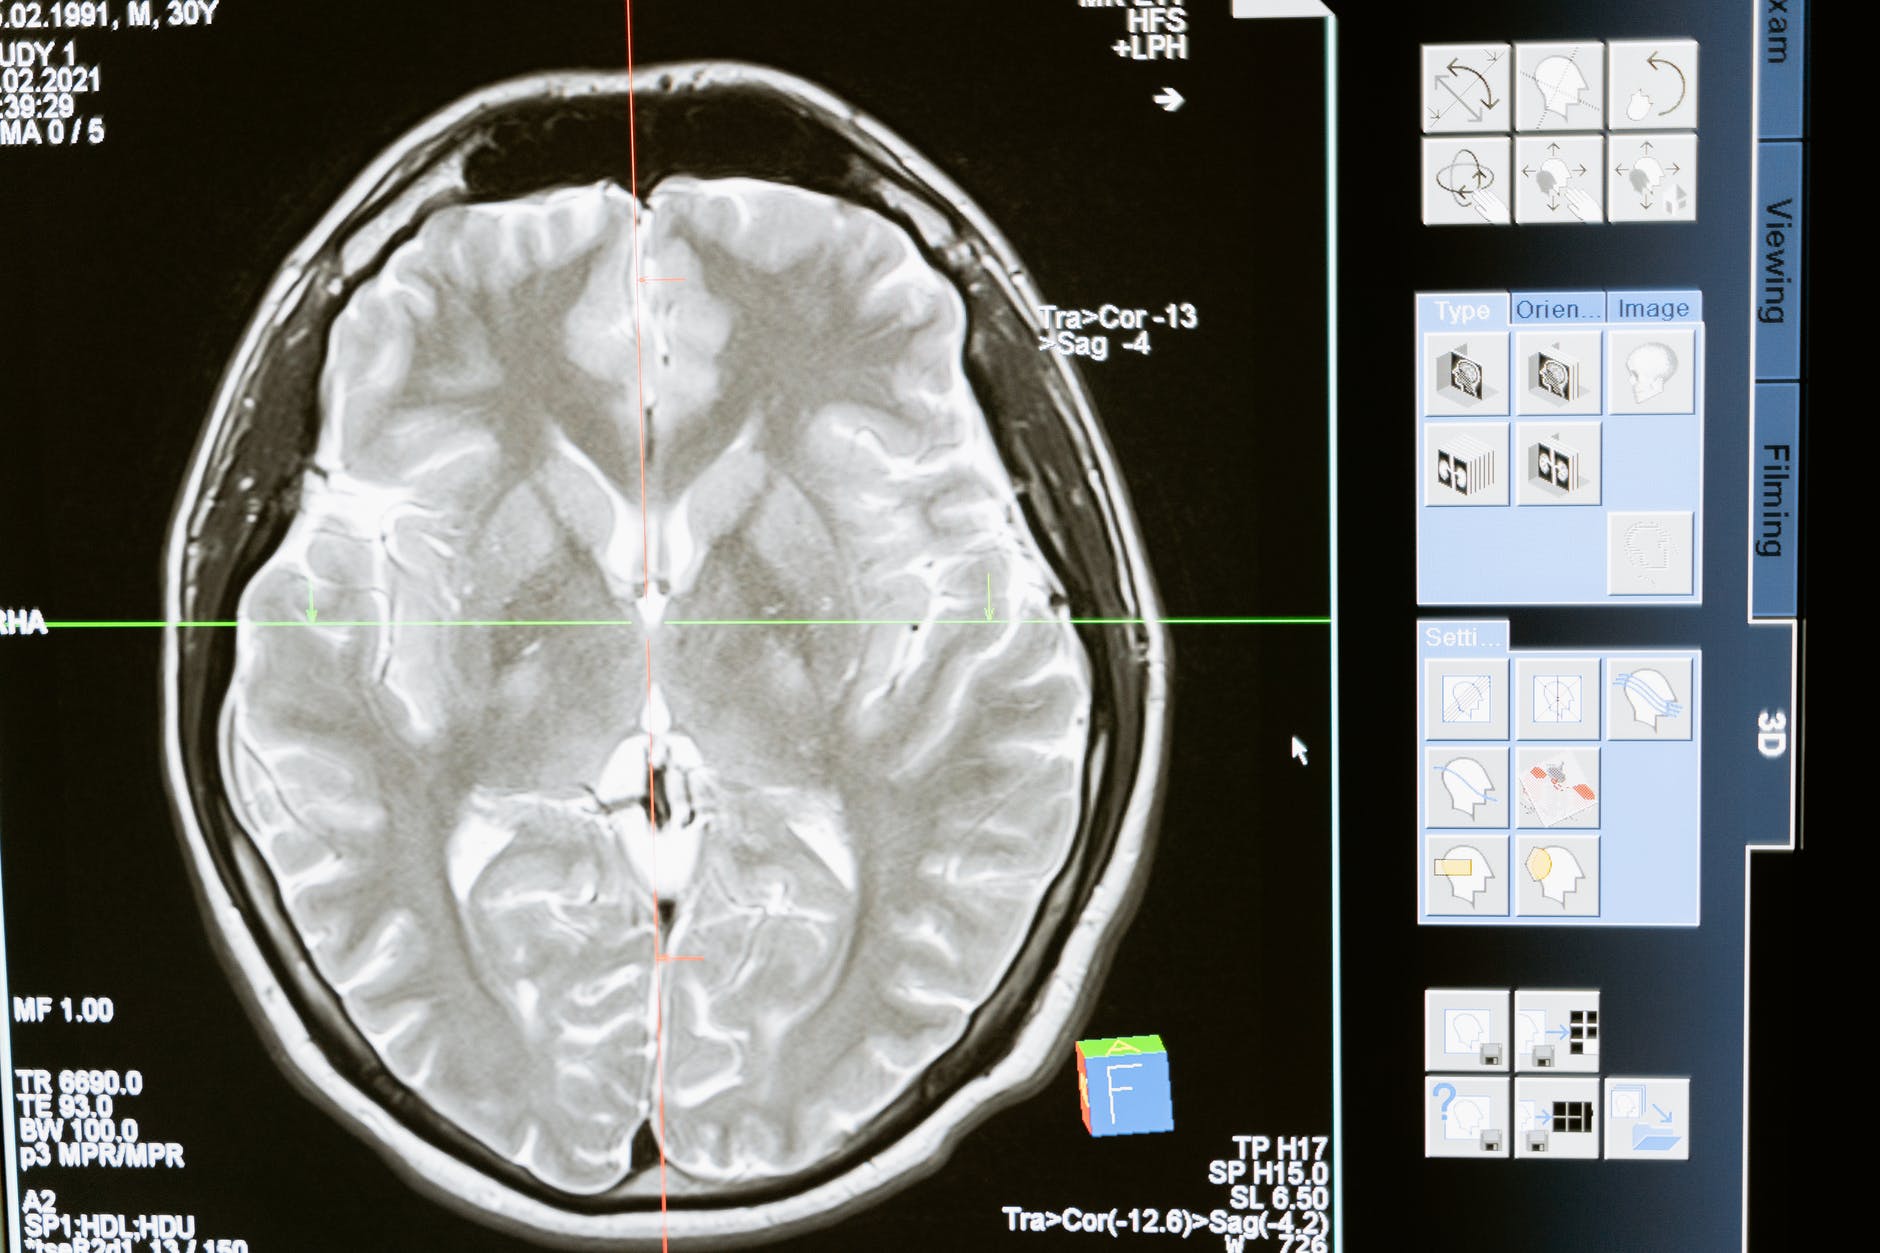

Of course, the best thing to do would be to maintain a healthy lifestyle to avoid the occurrence of a stroke. The most modifiable influences are tobacco use and high blood pressure. It’s estimated that 4/10 people that suffer from a stroke that the incident could have been prevented by regulation of blood pressure. There are two types of stroke; ischemic (where blood vessels are blocked by clots, fatty deposits called plaque, or other particles, thus cutting off oxygen to the brain) and non-ischemic/hemorrhagic (a weak blood vessel bursts and bleeds into the brain).